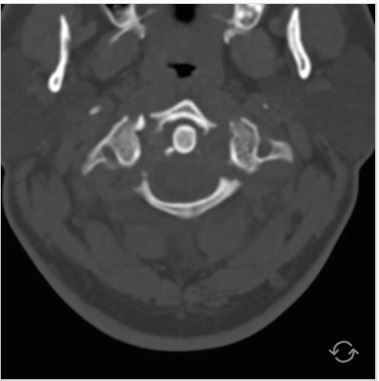

Q

what is this and what is it called?

A

bilateral # pars articularis

hangman #